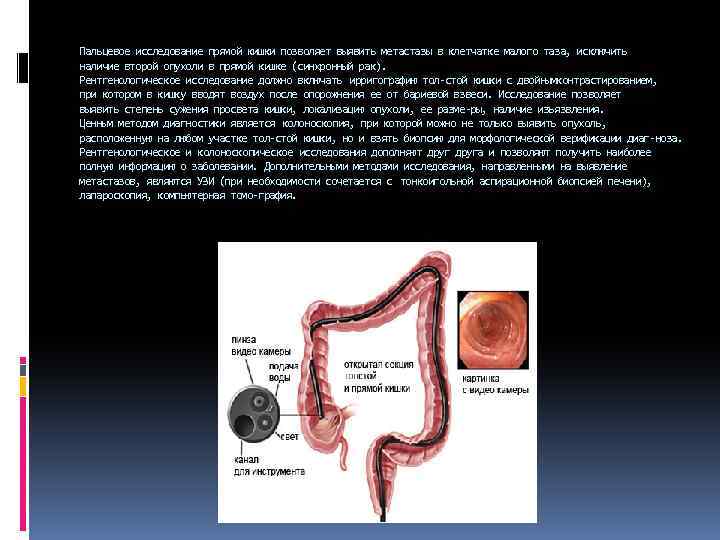

Пальцевое исследование прямой кишки позволяет выявить метастазы в клетчатке малого таза, исключить наличие второй опухоли в прямой кишке (синхронный рак). Рентгенологическое исследование должно включать ирригографию тол стой кишки с двойнымконтрастированием, при котором в кишку вводят воздух после опорожнения ее от бариевой взвеси. Исследование позволяет выявить степень сужения просвета кишки, локализацию опухоли, ее разме ры, наличие изъязвления. Ценным методом диагностики является колоноскопия, при которой можно не только выявить опухоль, расположенную на любом участке тол стой кишки, но и взять биопсию для морфологической верификации диаг ноза. Рентгенологическое и колоноскопическое исследования дополняют друга и позволяют получить наиболее полную информацию о заболевании. Дополнительными методами исследования, направленными на выявление метастазов, являются УЗИ (при необходимости сочетается с тонкоигольной аспирационной биопсией печени), лапароскопия, компьютерная томо графия.